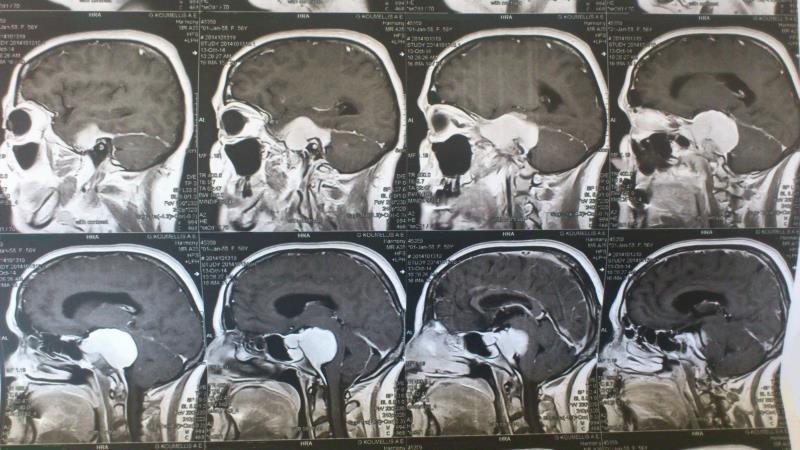

Ασθενής γυναίκα ηλικίας 56 ετών προσήλθε λόγω αστάθειας βάδισης, έκπτωσης ακουστικής οξύτητας αριστερά, αιμωδιών προσώπου κατανομής V2-V3 αριστερά και διπλωπίας ( ήπια πάρεση κοινού κινητικού ) . Ο προεγχειρητικός απεικονιστικός με μαγνητική τομογραφία εγκεφάλου ανέδειξε εικόνα συμβατή με μηνιγγίωμα αποκλίματος και λιθοειδούς ( petroclival ) , με επέκταση στο Meckel's cave και στον αριστερό σηραγγώδη κόλπο καθ' όλη την έκτασή του. Λόγω μεγάλου μεγέθους και έκτασης του μηνιγγιώματος αποφασίστηκε η αφαίρεσή του σε 2 στάδια. H προεγχειρητική αγγειογραφία ανέδειξε  υπολειπόμενο τον αριστερό εγκάρσιο κόλπο με έντονο παράπλευρο δίκτυο  με δυνατότητα εκτομής  του (transsinus ), αποφεύγοντας τις διαλιθοειδικές προσπελάσεις και την συνοδό νοσηρότητά τους. Η ασθενής είχε ομαλή μετεγχειρητική πορεία με βελτίωση της αστάθειας βάδισης και της ακουστικής οξύτητας. Ο μετεγχειρητικός απεικονιστικός έλεγχος ανέδειξε αφαίρεση του τμήματος του όγκου στον οπίσθιο κρανιακό βόθρο.

Μετεγχειρητικός απεικονιστικός έλεγχος